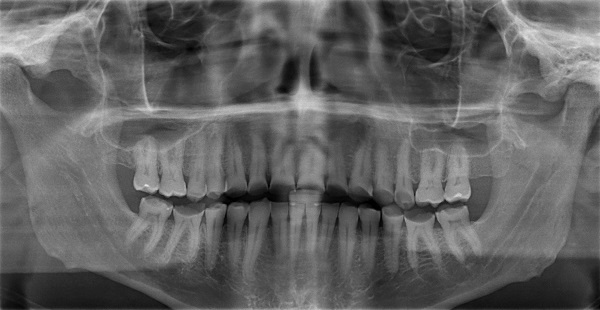

Dental imaging of the writer’s teeth (which are the least of the reasons why the doctor who is mentioned parenthetically below, Ray Bredfeldt, should burn in hell)

I went to the dentist for the first time in over a decade last week to be informed I grind my teeth in my sleep, and evidently have done for some while. This is among the possible consequences of chronic stress—to say nothing of, for example, cancer or heart disease or carelessly (or deliberately) wrapping your vehicle around a phone pole.

The dentist’s urgent recommendation was a full set of crowns, which he estimated would run me in the neighborhood of a “pretty good new car.” My own vehicle has in excess of 170,000 miles on it. I settled for a cleaning, which itself overextended my resources.